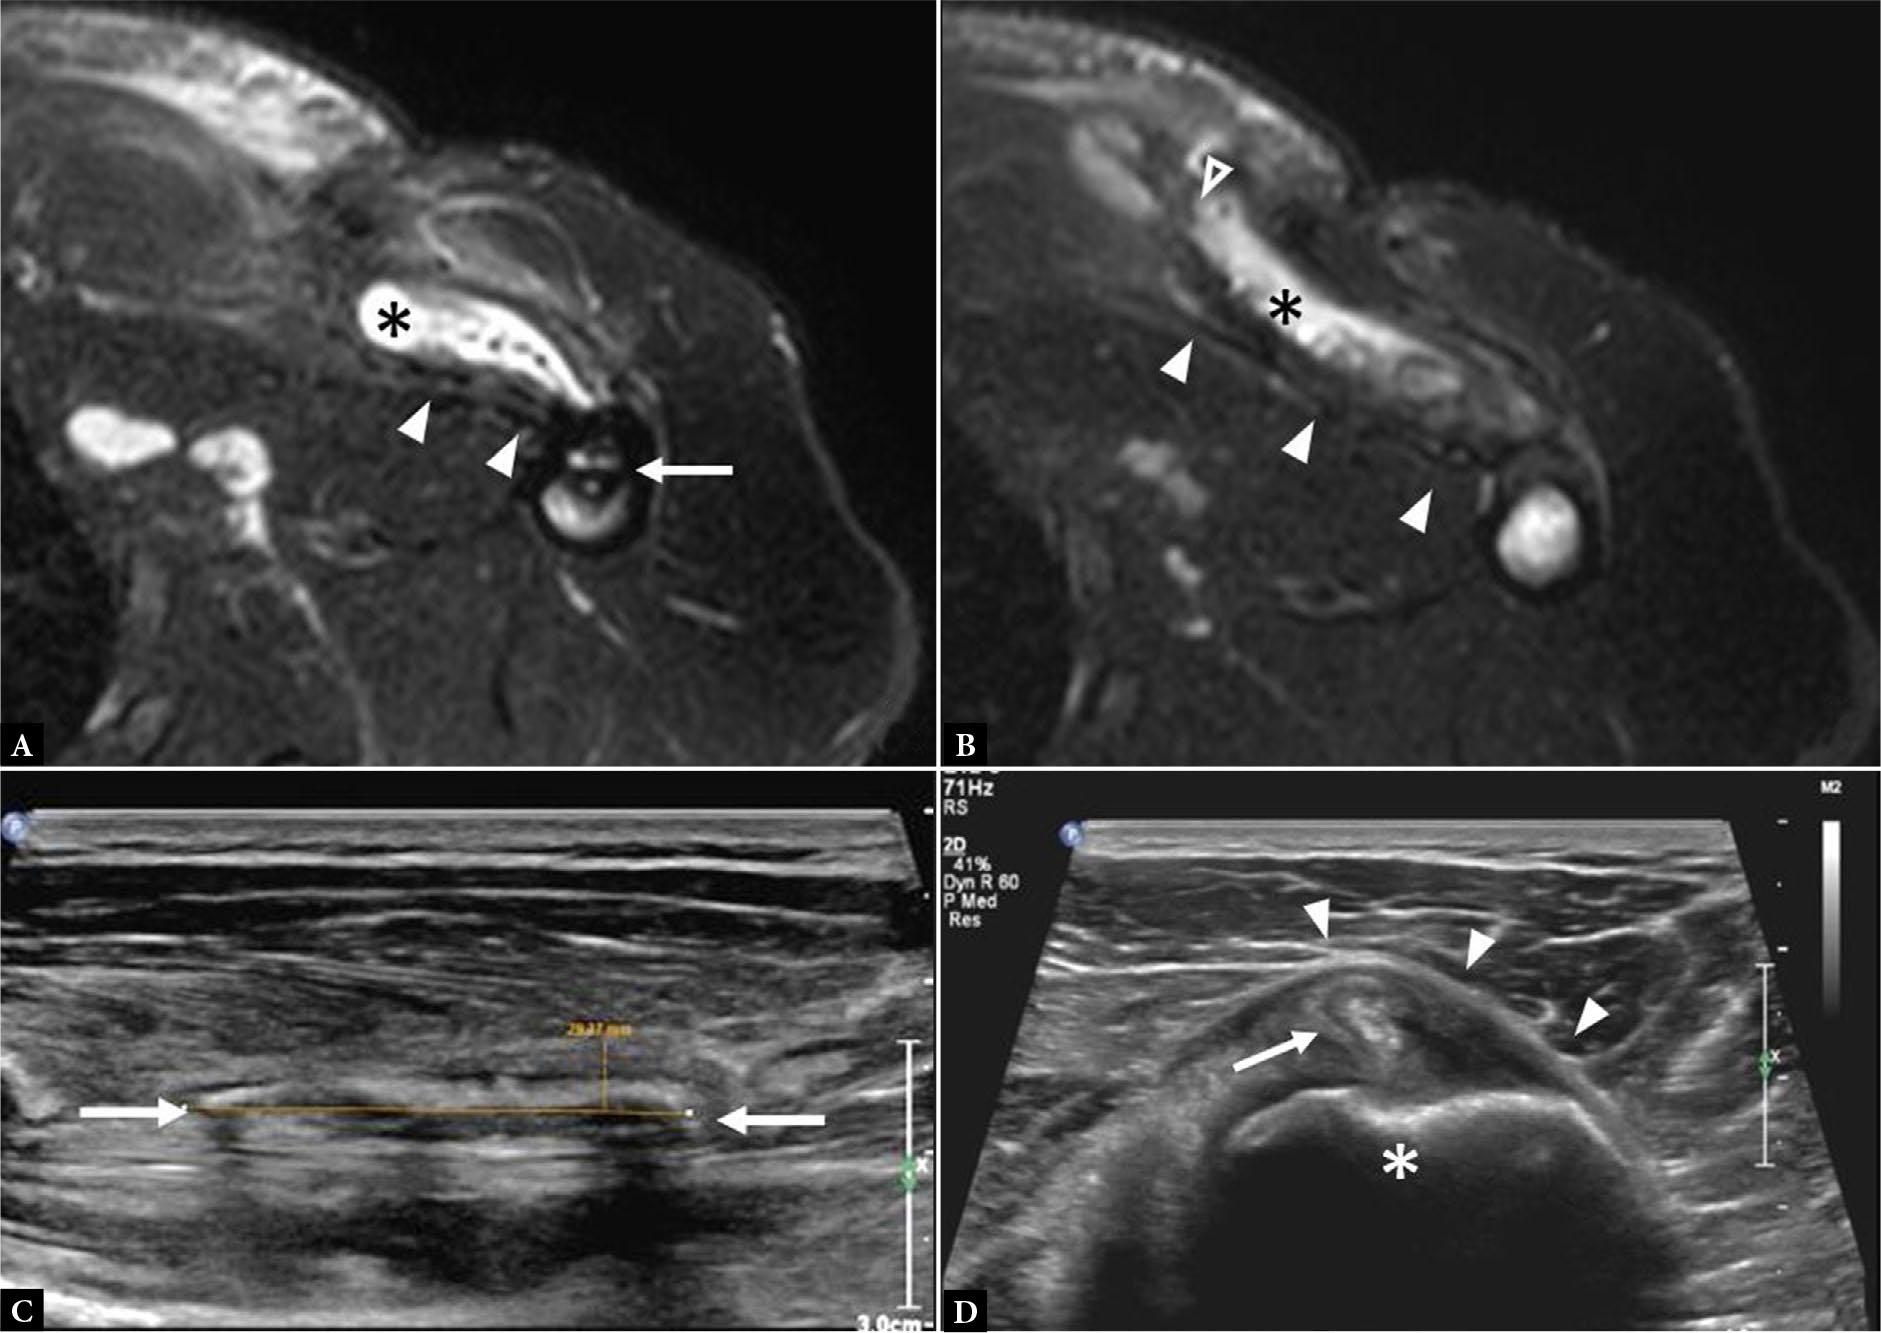

Fig. 7.

A. Coronal fluid-sensitive MR image shows a PM tear at the clavicular head origin with edema (arrowheads) interposed between the clavicle (asterisk) and the muscle. B. Axial fluid-sensitive MR image shows a PM tear at the myotendinous junction (between empty arrowheads) with edema, fiber disorganization, and surrounding poorly organized hematoma (asterisks). Note intact tendon insertion onto the humerus (solid arrowheads). C. Short axis gray scale ultrasound image shows feathery anechoic fluid (arrows) tracking along the expected course of the pectoralis muscle fibers in the setting of intramuscular PM tear (not shown). D. Coronal fluid-sensitive MR image shows an intramuscular PM tear with edema and discontinuous fibers (arrowheads). E. Long axis gray scale ultrasound image shows an intramuscular PM tear with intramuscular edema at the site of tear (arrowheads) and more focal anechoic abnormality that represents a small intramuscular hematoma (asterisk)